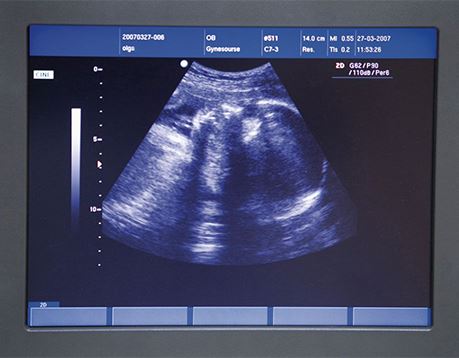

It's a girl! The gender and developmental progress of unborn babies is just one kind of information that diagnostic medical sonography provides for doctors and their patients. Sonographers use sophisticated sound technology to create images that help physicians monitor pregnancies and other conditions and diseases within the human body. If you enjoy working with both people and technology, have good physical stamina and an analytical eye, and aim for a career in health care, then a career as an ultrasound technician may be for you. If you imagine yourself in a career working hands-on in a clinical setting providing care and vital information for patients and doctors, read on to learn more about our program.

- OB/GYN Sonography

Prepare for a career in the medical imaging field through this associate-degree program. Gain a thorough knowledge of anatomy, cross-sectional anatomy and pathology, as well as the skills to manipulate a wide variety of sophisticated instruments. This program is accredited by the Commission on Accreditation of Allied Health Educational Programs.